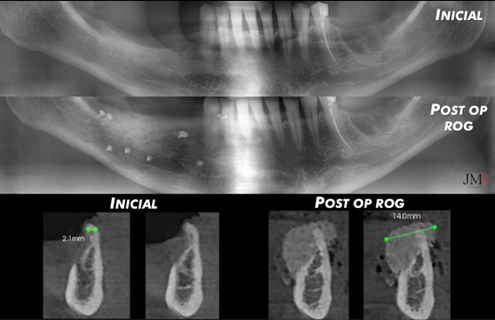

Collage de la situación inicial y la regeneración realizada usando MatrixFlex, MatrixOss e injerto autógeno.

Figura 14.

Comparación situación radiográfica inicial y tras realizar la regeneración ósea guiada (ROG).